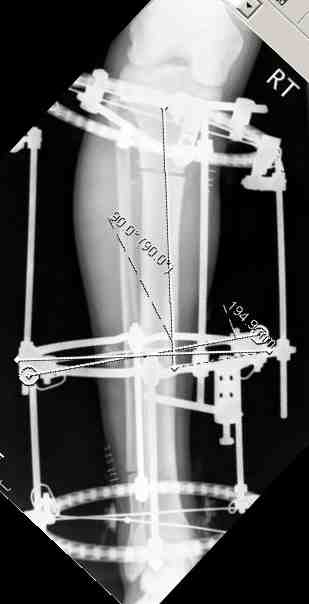

В нижнем ряду представлены рентгенограммы после окончательной репозиции.

And final reduction after Hexapod program has been finished

Одновременное и точное исправление многоплоскостной деформации является очень важным моментом, который трудно даётся при применении аппарата Илизарова, особенно при сочетании с ротационной деформацией. В этом случае гексаподный аппарат Илизарова незаменим.

Simultaneous and exact correction of multilane deformities combined with rotation is very important and difficult to accept at application of Ilizarov apparatus. In these cases Ilizarov hexapod apparatus is irreplaceable.